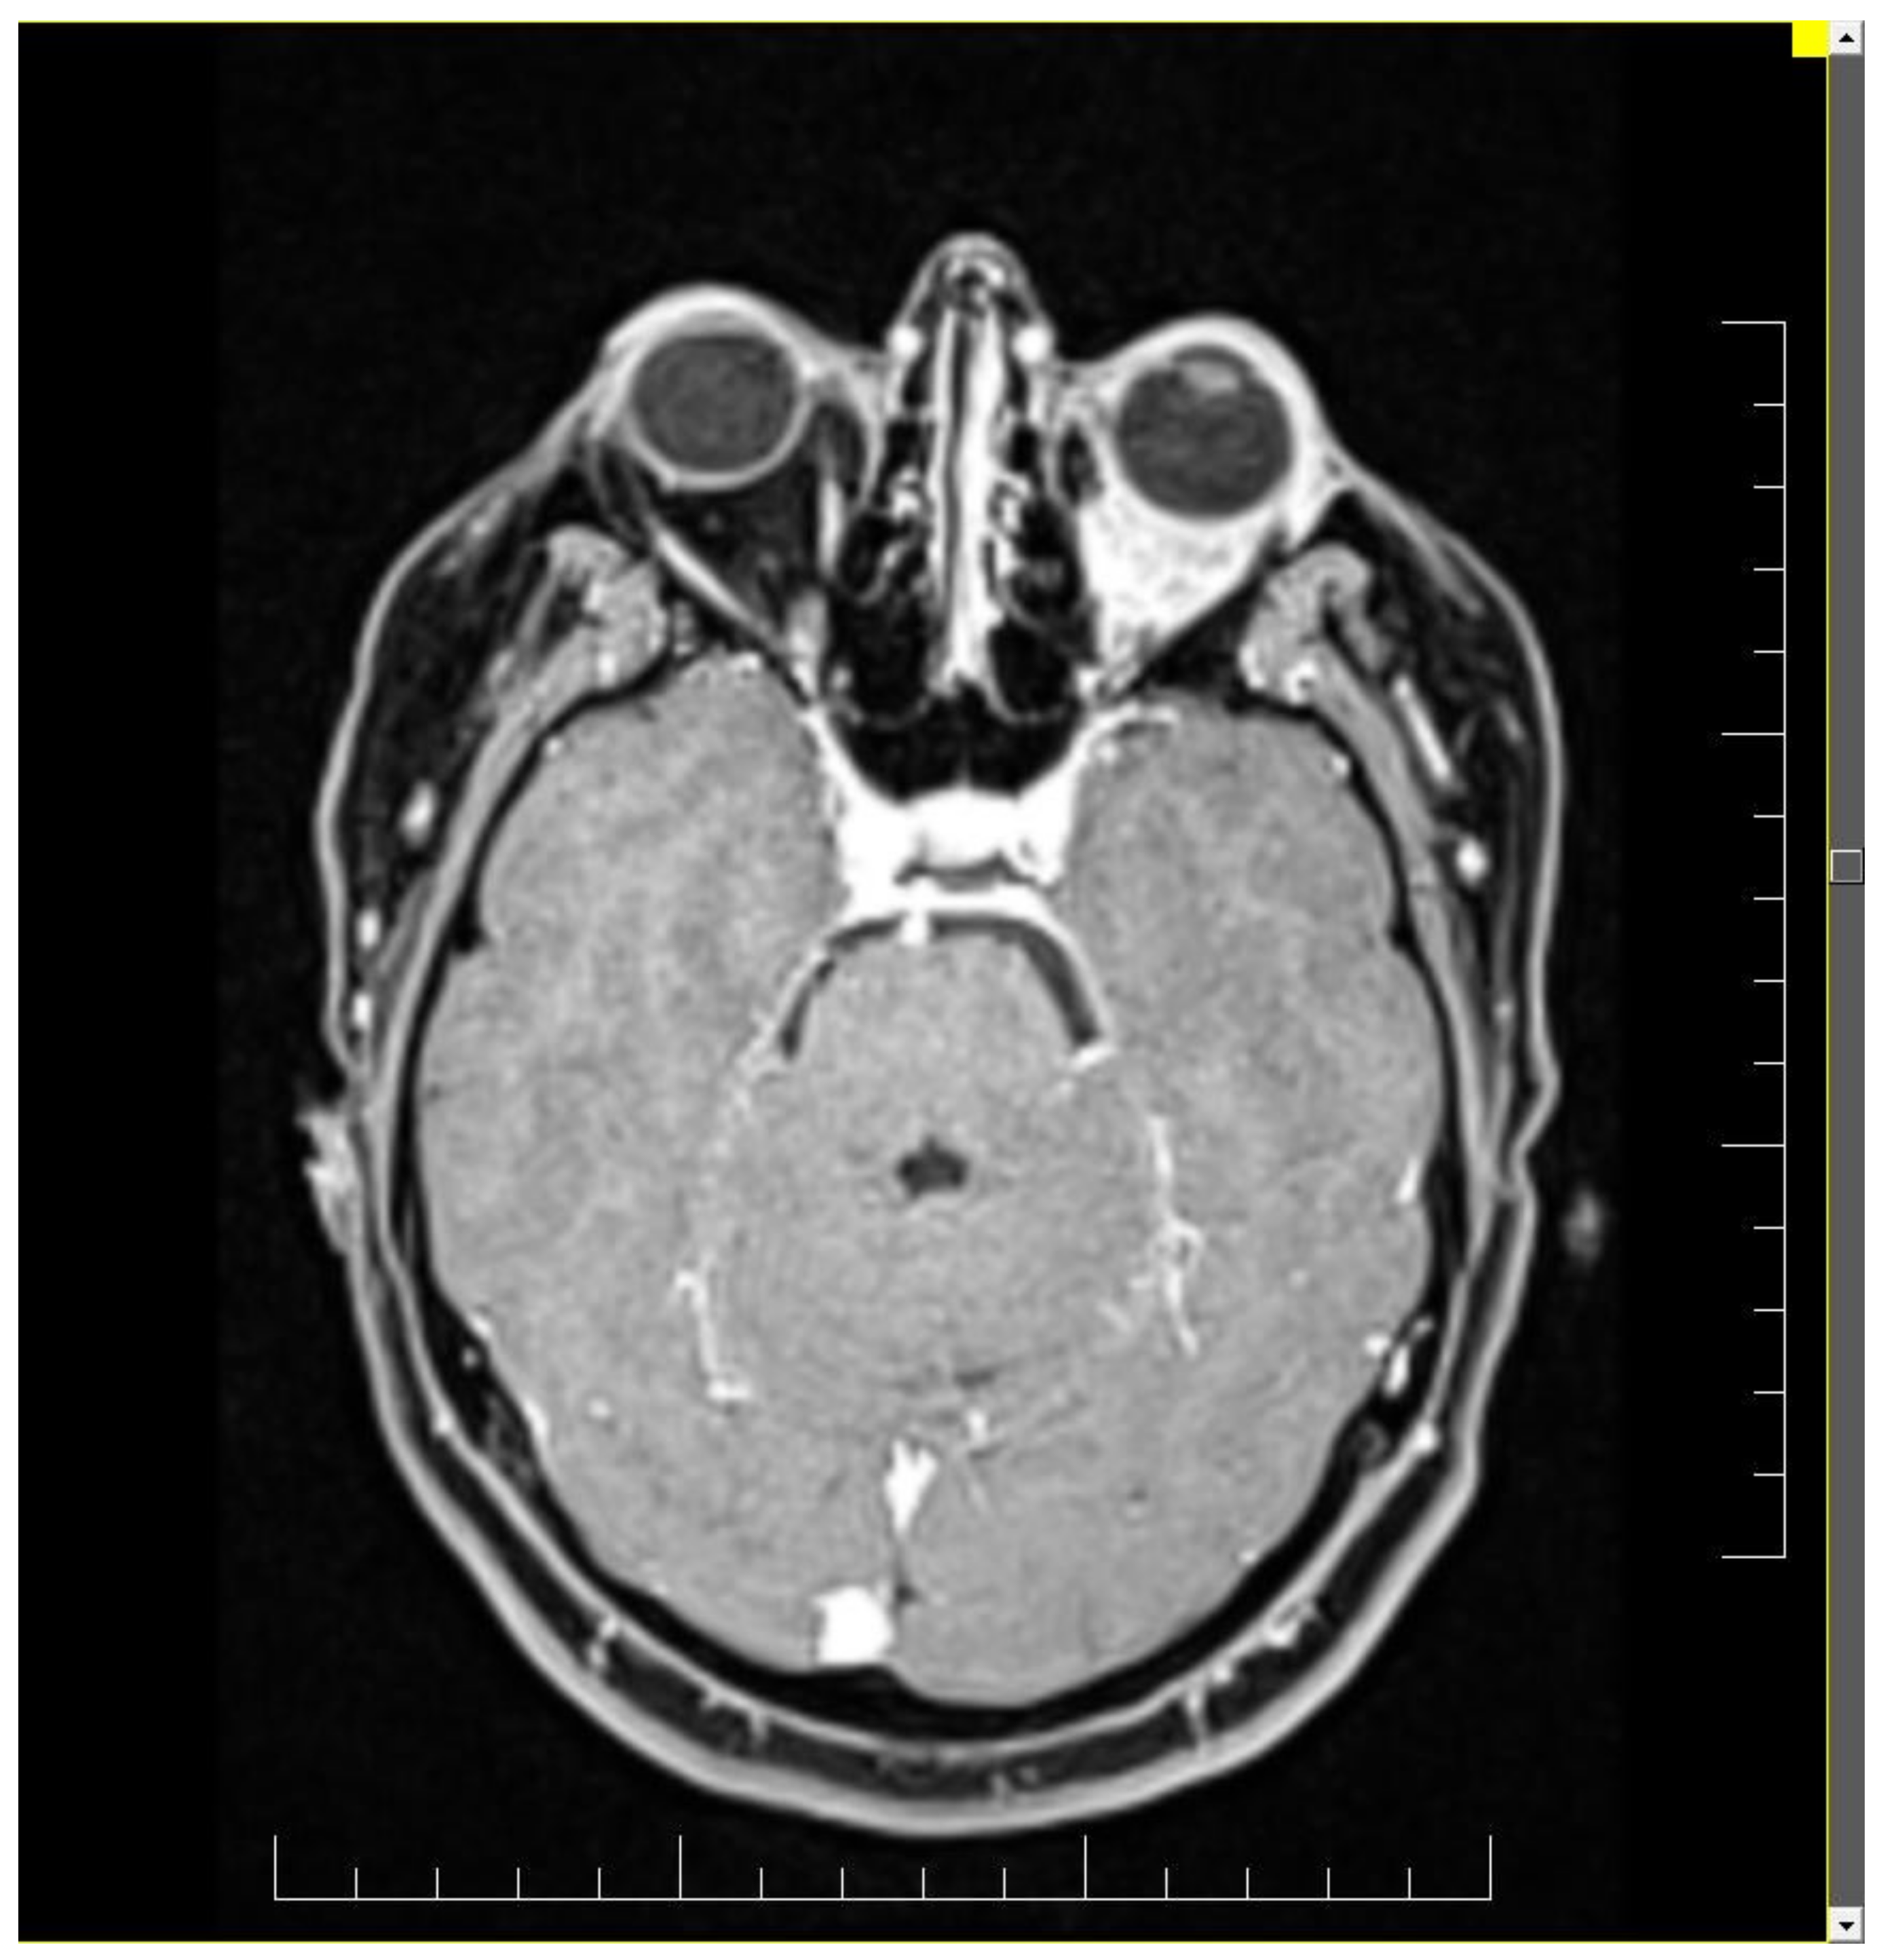

Ophthalmologic and neurologic examinations revealed reduced visual acuity, reduced mobility in all directions of the eye, normal intraocular pressure, hypoesthesia of the left hemi-face, paresis of the 3rd and 4th nerve of the left eye and paresis of the 5th nerve. Magnetic resonance imaging (MRI) and computed tomography (CT) scan detect a tumor situated in the left retroocular space in the intraconal area, which cuffs the left optic nerve and invades the extra-ocular muscles (Figure 1 and Figure 2). Differential diagnosis included diabetic retinopathy, thyroid ophthalmopathy, lymphoma, primary or metastatic neoplasia. The thyroid function tests were normal and the ophthalmologic exam excluded diabetic retinopathy.

MRI is the gold standard for evaluating orbital tumors because this ensures a better contrast of the soft tissue and does not afflict ionizing radiation. Imaging patterns such as the appearance of a mass accompanied by muscular or fatty infiltration generally suggests the presence of a mammary carcinoma metastasis, osseous affection indicates the existence of prostate cancer and prevailing muscular affliction reveals a melanoma. Mainly, orbital metastases are located exclusively in extraconal spaces (50%) and the rest are found either in intraconal spaces (30%) or in both (20%) [14]. The execution of diffusion weighted imaging can improve the differential diagnosis between an orbital process and a benign tumor (such as a hemangioma), sarcoidosis, Wegener granulomatosis and lymphoproliferative disorders. If the T2-weighted images series shows hypointense signals it may correspond to an inflammatory pseudo tumor, while hyperintense lesions may reveal a lymphoma or metastasis [14,15].

Figure 2. Brain MRI exhibiting a left retroocular intraorbital tumor, which infiltrated the ocular muscles in three out of quarter quadrants.